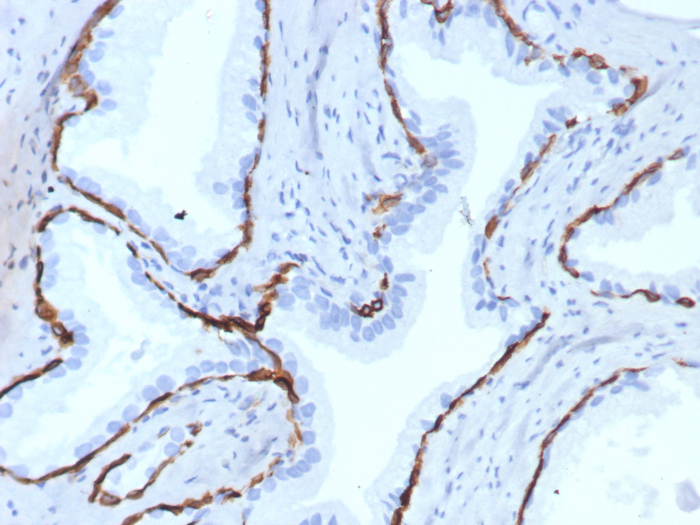

Formalin-fixed, paraffin-embedded human prostate stained with Cytokeratin 14 antibody (KRT14/7977R). HIER: Tris/EDTA, pH9.0, 45min. Secondary: HRP-polymer, 30min. DAB, 5min.

Immunohistochemistry (Formalin-fixed): 1-2ug/ml for 30 minutes. at RT. Staining of formalin-fixed tissues requires heating tissue sections in 10mM Tris with 1mM EDTA, pH 9.0, for 45 min at 95C followed by cooling at RT for 20 minutes.